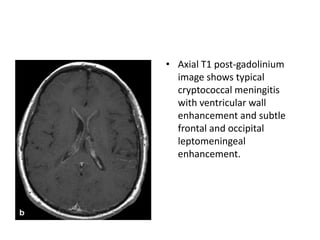

• Axial T1 post-gadolinium

image shows typical

cryptococcal meningitis

with ventricular wall

enhancement and subtle

frontal and occipital

leptomeningeal

enhancement.

• Axial T1post-gadolinium image shows typical cryptococcal meningitis with ventricular wall enhancement and subtle frontal and occipital leptomeningeal enhancement.